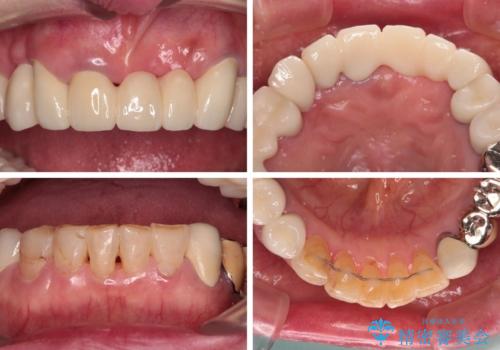

処置を予定していた歯を仮歯に変えた時点で、下顎前歯の部分矯正を行うかどうかを尋ねたところ、折角なので行いたいと言うことでしたので、矯正治療を行うこととしました。

インプラント埋入や根管治療治療など、治癒に一定の期間を要する処置の合間に矯正治療を行うことで、効率的に治療を進めて行くことができました。